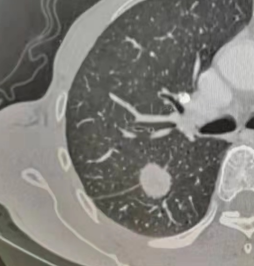

▲根据结节的密度,可以分为

纯磨玻璃结节(类似荔枝果肉)、混合磨玻璃结节(类似荔枝果肉与果核并存)(恶性风险较高)、实性结节(类似荔枝果核)。

纯磨玻璃结节 | 混合磨玻璃结节 | 实性结节 |